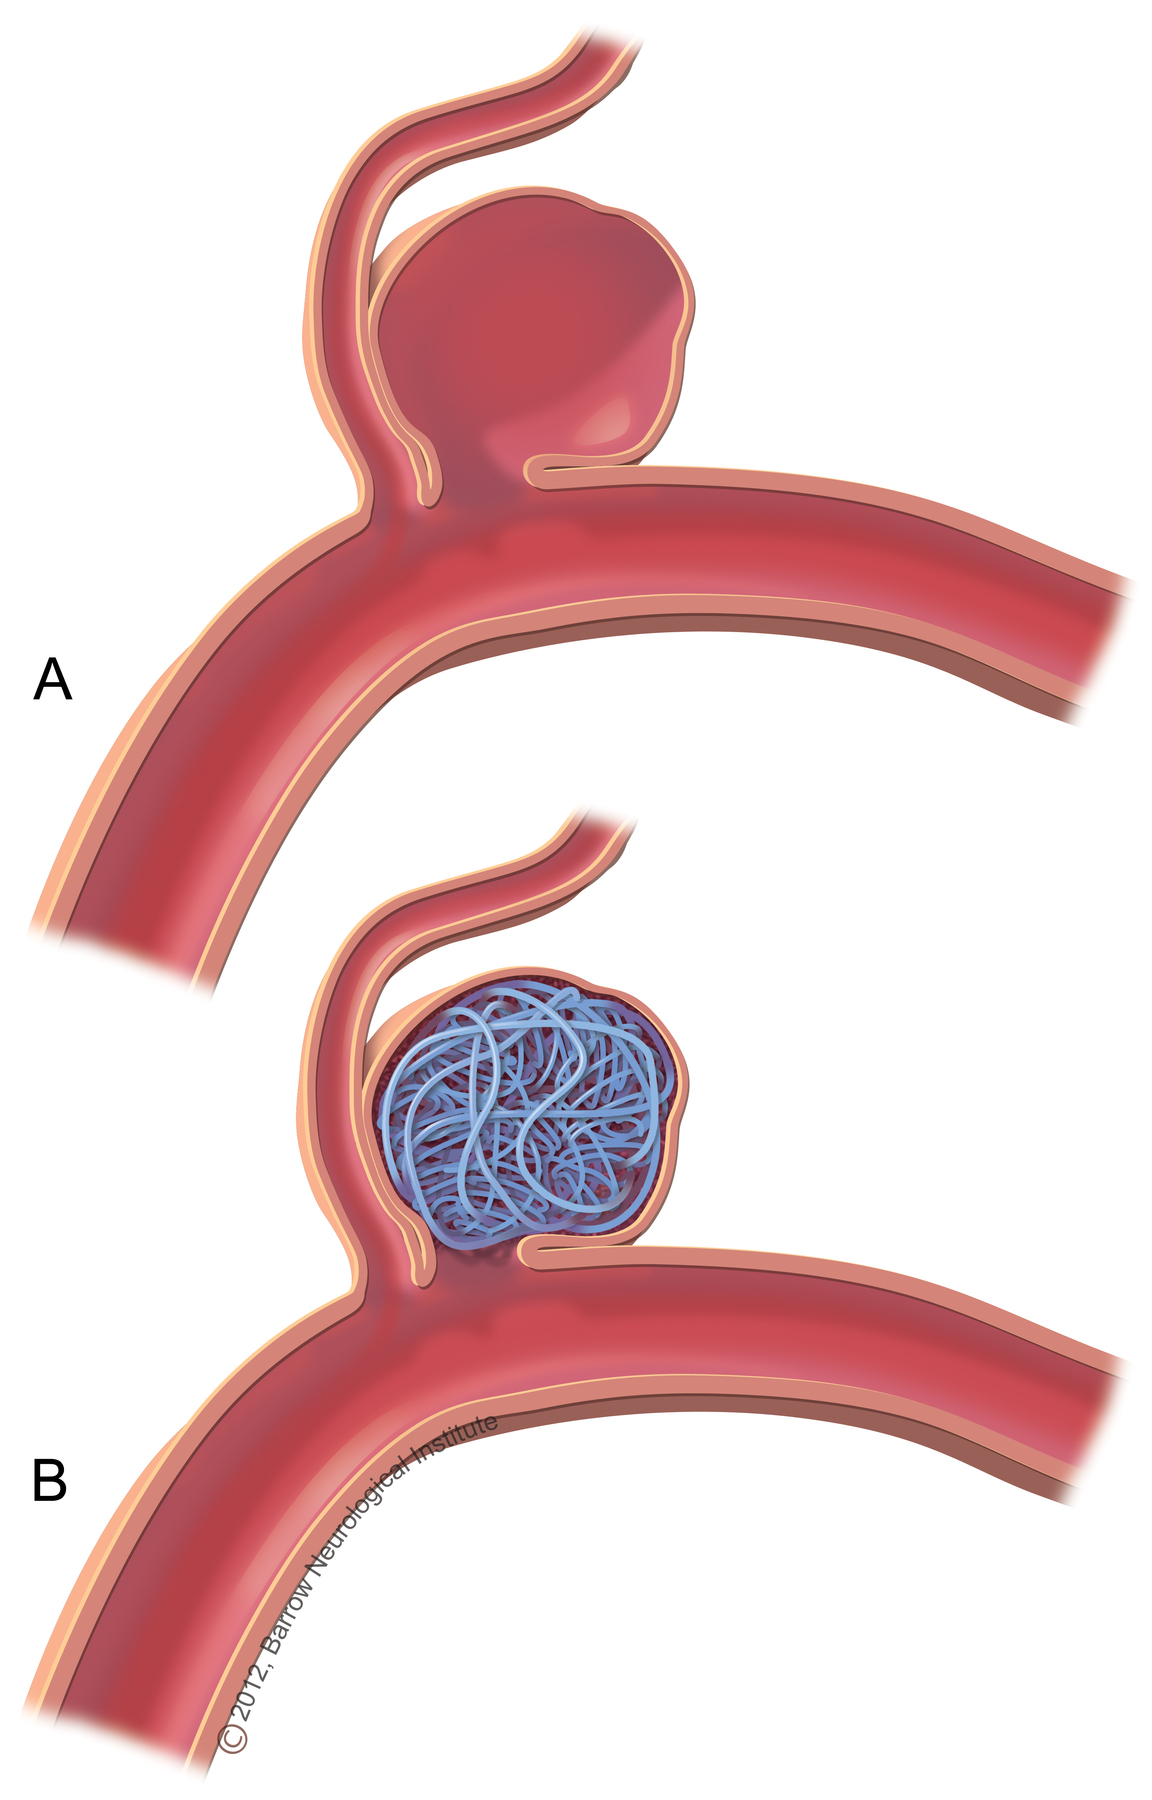

Снимки и иллюстрации микроаневризм сосудов головного мозга